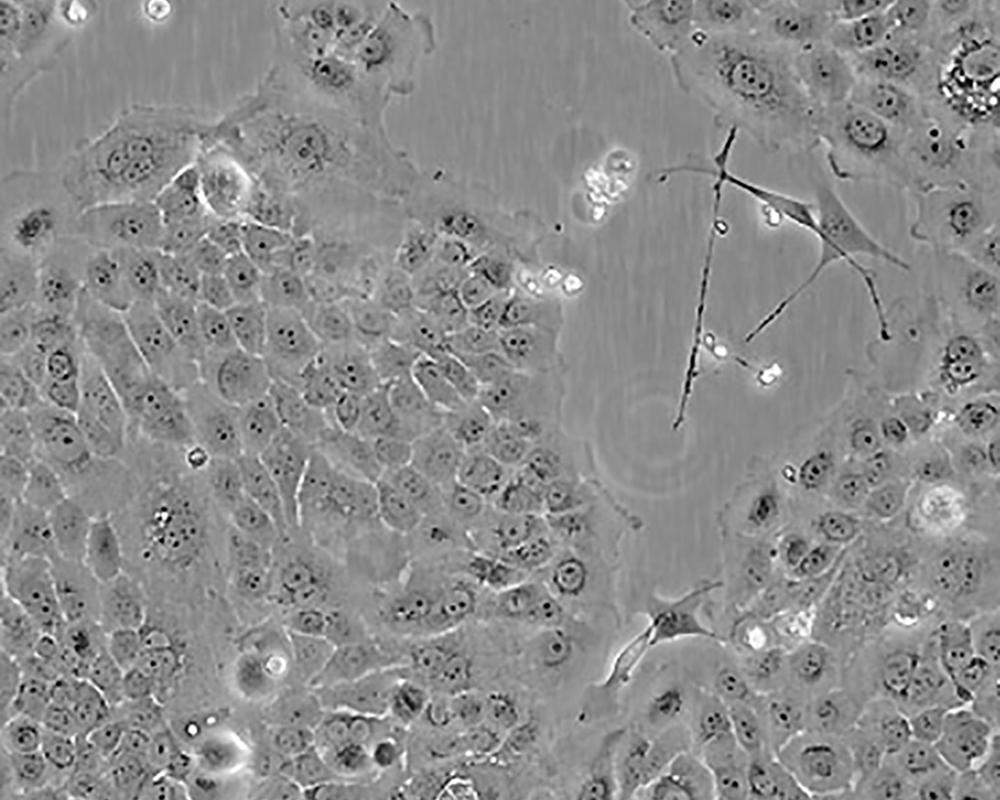

BxPC-3(BxPC3)

產(chǎn)品名稱 BxPC-3(BxPC3)

中文名稱 人原位胰腺腺癌細(xì)胞

組織來源 胰腺導(dǎo)管腺癌;女性

生長特性 adherent

形態(tài)特征 epithelial

細(xì)胞描述 The cells do not express the cystic fibrosis transmembrane conductance regulator(CFTR). A CFTR positive pancreatic line, Capan-1 is available.